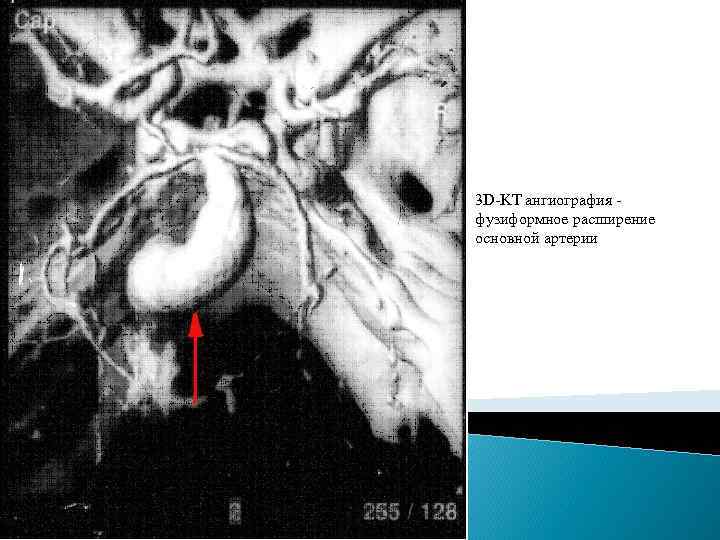

Классификация аневризм. Существует множество классификаций аневризм головного мозга, наиболее распространенные из них – классификация по форме, величине и артерии, на которой они расположены. Классификация аневризмы по форме. 1. Мешотчатые (одно- или многокамерные). 2. Веретенообразные (фузиформные). Классификация аневризм по артерии, на которой они расположены. 1. На передней мозговой – передней соединительной артериях (45 %). 2. На внутренней сонной артерии (32%). 3. На средней мозговой артерии (19%). 4. На артериях вертебро-базилярной системы (4%) 5. Множественные аневризмы – на двух и более артериях (13%). Классификация аневризм по величине. 1. До 3 мм – милиарные. 2. 4 - 15 мм – обычные. 3. 16 - 25 мм – большие. 4. Более 25 мм – гигантские.

3 D-KT ангиография - фузиформное расширение основной артерии